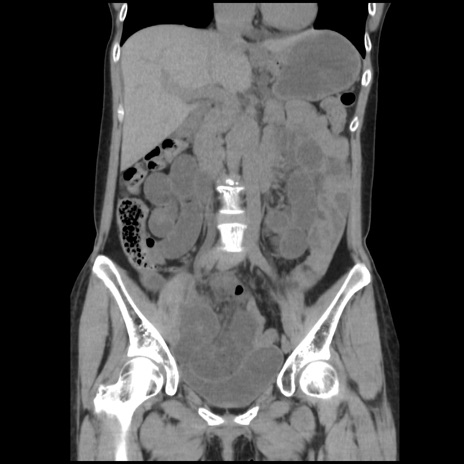

症例32(冠状断像)

【症例】40歳代 女性

【主訴】上腹部痛、嘔気・嘔吐

【現病歴】約9時間前頃から急に上腹部痛、嘔気、嘔吐が出現。改善しないため救急要請。

【既往歴】子宮頚癌(広汎子宮全摘術、放射線療法)、腸閉塞

【身体所見】腹部:平坦、軟、腸雑音亢進、上腹部を中心に腹部全体に圧痛あり。

【データ】WBC 8400、CRP 0.03